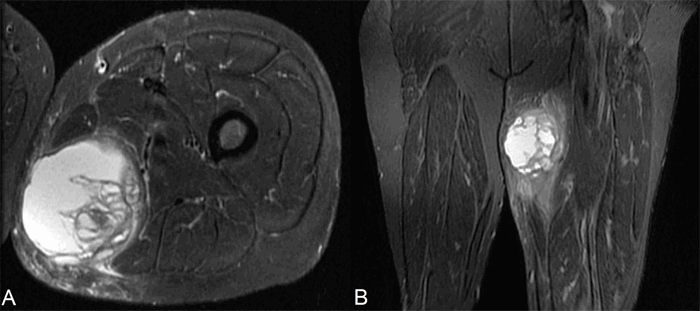

The patient reported continued swelling of the mass and increased pain in the left thigh over the next couple of weeks between examinations. Following a review of the initial pathology report with the consideration that he had undergone partial tumor resection, the patient was scheduled for radical resection of the remaining mass. Discussion regarding the use of neoadjuvant therapy was held; however, it was ultimately decided to resect first and offer adjuvant therapy. Before the surgery, the patient received magnetic resonance imaging (MRI), which located the mass between the gracilis and semimembranous muscle, suggesting that it likely originated in the adductor magnus muscle. The mass, measuring approximately 9.3 cm x 7.7 cm x 7.5 cm, was located 10 cm distal to the ischial tuberosity (Figure 1). A chest X ray further confirmed that there were no signs of metastatic disease. Subsequently, the patient underwent a radical resection of the left thigh mass measuring 25 cm x 15 cm x 10 cm with complex wound closure. The need for a large resection area was due to the combination of operating in a previously instrumented field and requiring negative margins in a patient who already underwent partial tumor resection.

Figure 1. A) The axial coronal view MRI of the femur using fast spin-echo inversion-recovery sequence (FSE-IR). B) The axial coronal view MRI of the femur using FSE-IR.